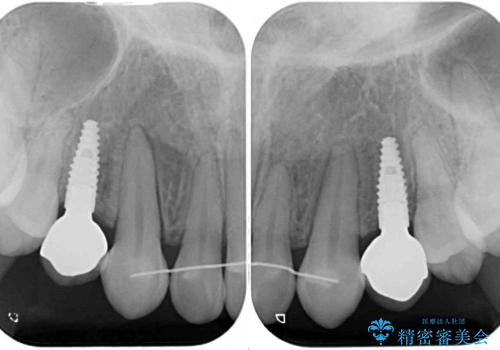

- 歯の欠損による隙間だらけの歯並びを気にして来院された患者様です。

上顎左右1本ずつ欠損していたため、歯列矯正により欠損部位にスペースを集め、その後欠損部位をインプラントにて補綴することとしました。

インビザラインによる矯正治療も提案しましたが、長時間の装着や自己管理が難しいとお考えで、ワイヤーによる矯正治療を行いました。

歯並びは比較的早めに整いましたが、インプラントを埋入するにあたって前後の歯根位置を改善する必要があり、矯正治療に期間を要することとなりました。